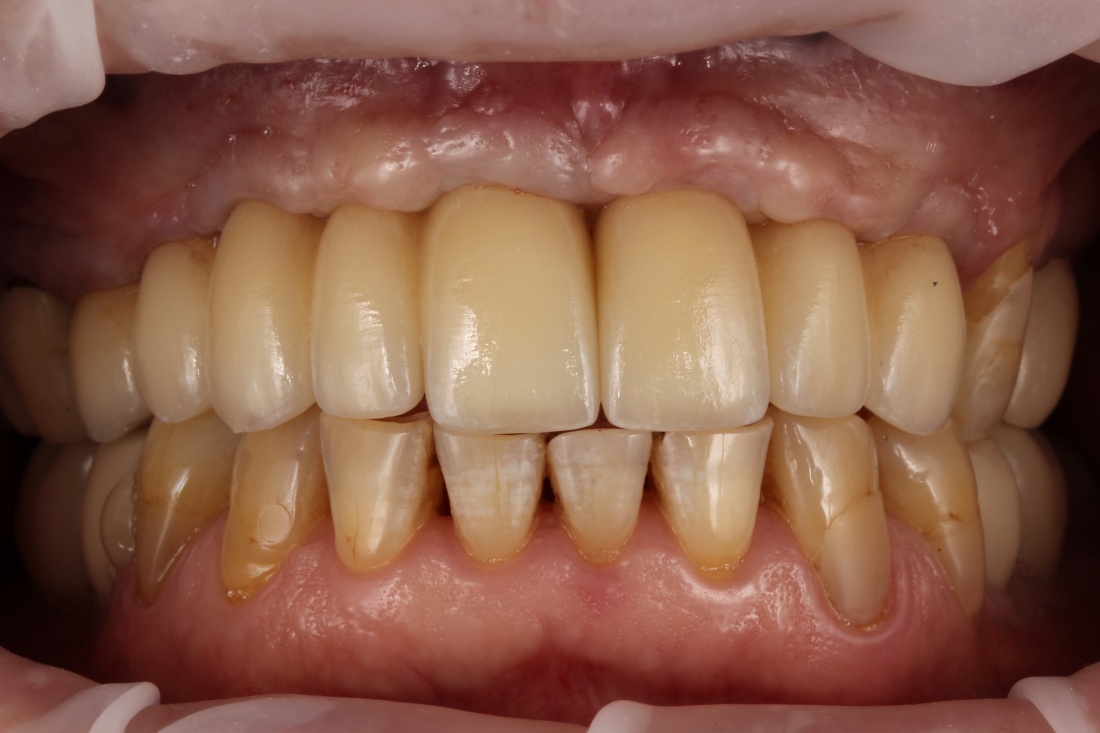

Рекомендации по установке имплантов. Для всех. Часть V.